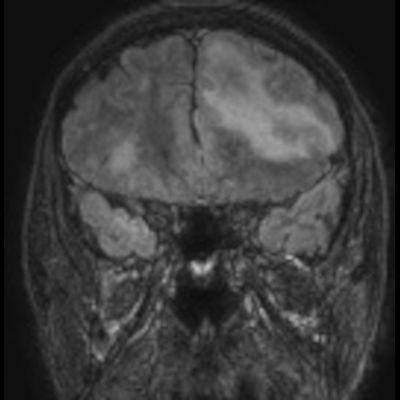

- Bilateral asimetrik subkortikal ve derin beyaz cevherde T1 ağırlıklı görüntülerde belirgin hipointens (oklar), T2A görüntülerde hiperintens (oklar), gri cevhere bakan kesimi düzgün (oklar), DAG’de hiperintens (ok) lezyonlar izlendi. Lezyonlarda T2/FLAIR uyumsuzluğu vardı (ok). Serebellar beyaz cevherde dentat nukleusu koruyan hilal işareti görüldü (ok başı). SWI sekansta sol motor kortekste hipointens kronik glioinflamatuar reaksiyon ile uyumlu sinyal değişikliği izlendi (ok başı).

- Çoğunlukla subkortikal beyaz cevherde ve U fiberlerde, asimetrik, genelde kitle etkisi yapmayan ve kontrastlanmayan demiyelinizan lezyonlar görülür. Korteks ve derin gri cevher tutulumu daha nadirdir.

- PML lezyonları, T1A görüntülerde belirgin hipointenstir. Gri cevhere bakan yüzleri keskin olup T2/FLAIR uyumsuzluğu önemli özelliğidir.

- PML lezyonlarında kronik olarak aktive olan glial hücreler ve mikroglia/makrofajlar sitoplazmalarında yüksek seviyelerde demir ve pigment içerebilir ve SWI da hipointens olarak görülür.